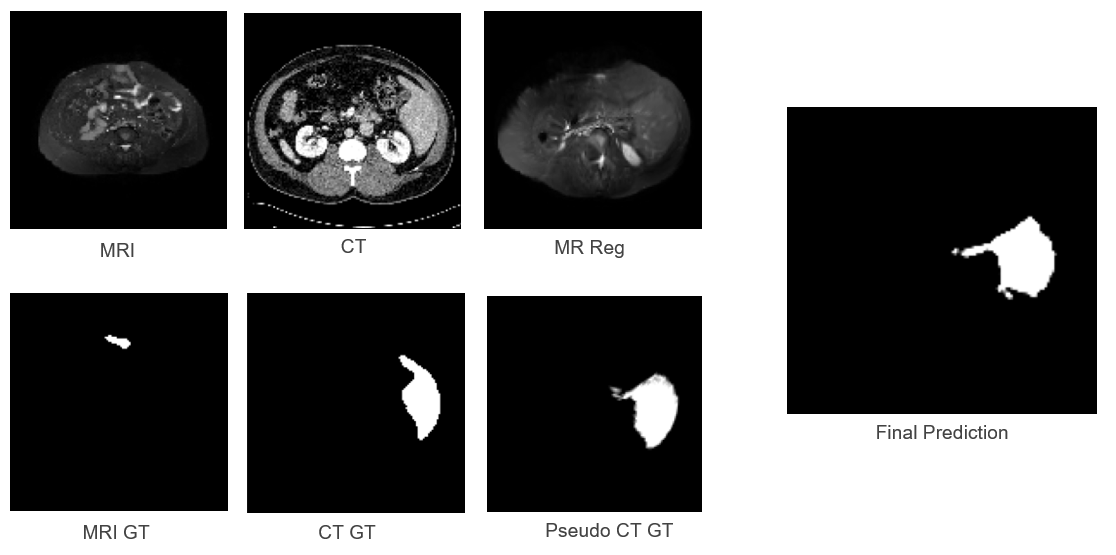

Figure 4 illustrates the pipeline stages for CHAOS data. The close similarity between CT_GT and Pseudo CT_GT confirms that registration is performed accurately. The final liver segmentation prediction demonstrates the viability of the approach for visible anatomical structures.

Refer to caption

Figure 4: CHAOS Results: Pipeline stages showing accurate registration and segmentation of healthy liver anatomy